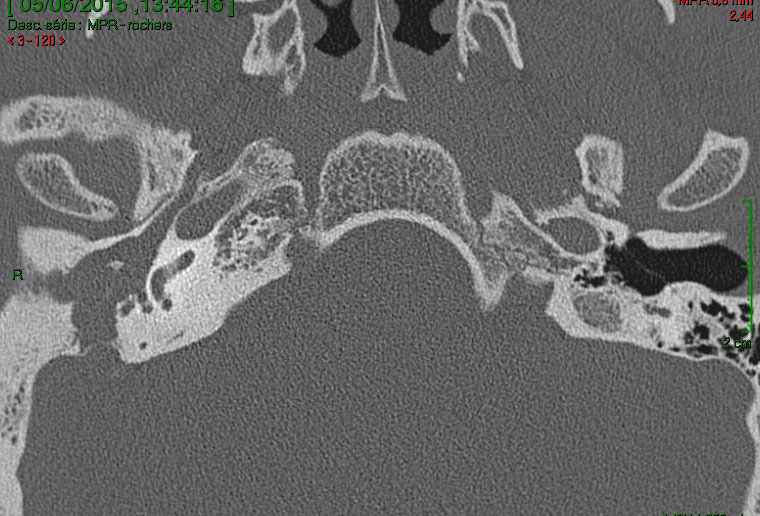

Devant ces atteintes multiples, vous demandez un scanner et une imagerie par résonance magnétique en urgence qui sont représentés ci-dessous.

Question 11 - Qu’en pensez-vous (une ou plusieurs réponses exactes) ?

La cavité de l’oreille est noire : donc il y a de l’air. Elle n’est pas comblée par du tissu.

Le scanner montre un comblement aspécifique, sans différencier tissu, liquide ou fibrose.

L’IRM est le seul examen pathognomonique du cholestéatome. Le scanner montre la lyse osseuse mais n’est pas du tout spécifique de l’atteinte. Il n’est pas nécessaire de connaître les structures de l’oreille interne sur le scanner (qui sont très compliquées), mais il faut au moins reconnaître une oreille moyenne pleine (contenu gris) d’une oreille saine aérée (contenu en noir). On peut ensuite déduire de l’énoncé les destructions correspondantes. On aurait pu aussi dire dans cette question que le canal du nerf facial était détruit : c’est forcément le cas puisqu’il y a une atteinte du facial.